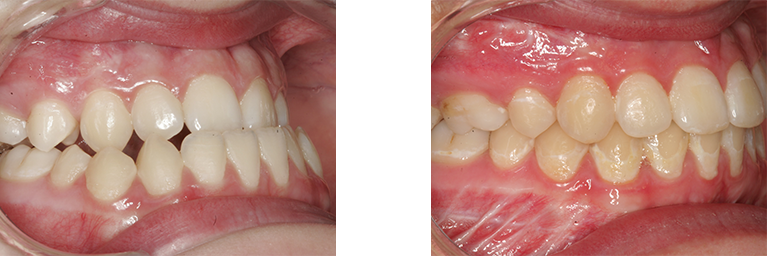

Person med underbid